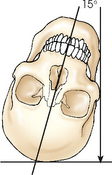

In an axial projection (Fig. 3-27), there is longitudinal angulation of the central ray with the long axis of the body or a specific body part. This angulation is based on the anatomic position and is most often produced by angling the central ray cephalad or caudad. The longitudinal angulation in some examinations is achieved by angling the entire body or body part while maintaining the central ray perpendicular to the IR.

Fig. 3-27 AP axial projection of skull. Central ray enters anterior aspect at an angle and exits posterior aspect.

The term axial, as used in this atlas, refers to all projections in which the longitudinal angulation between the central ray and the long axis of the body part is 10 degrees or more. When a range of central ray angles (e.g., 5 to 15 degrees) is recommended for a given projection, the term axial is used because the angulation could exceed 10 degrees. Axial projections are used in a wide variety of examinations and can be obtained with the patient in virtually any body position.